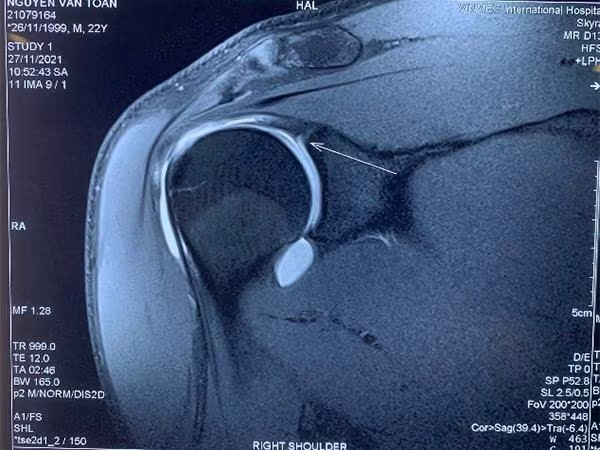

![]() |

Phim MRI khi có tiêm thuốc thấy rõ tổn thương hơn |

Các bác sĩ cho rằng khả năng đây là tổn thương SLAP vai phải - thương tổn có cơ chế là lực truyền từ cánh tay qua khớp vai đang bị rách, bong khớp, rất phù hợp với kiểu vận động cánh tay đặc thù của thủ môn. Qua phim chụp MRI cản quang và thăm khám lâm sàng, GS Dũng cùng các bác sĩ đã đưa ra kết luận Văn Toản bị chấn thương cơ nhị đầu, cụ thể là bị tổn thương một phần chân bám của cơ nhị đầu cũng như sụn viền chỗ chảo khớp vai.